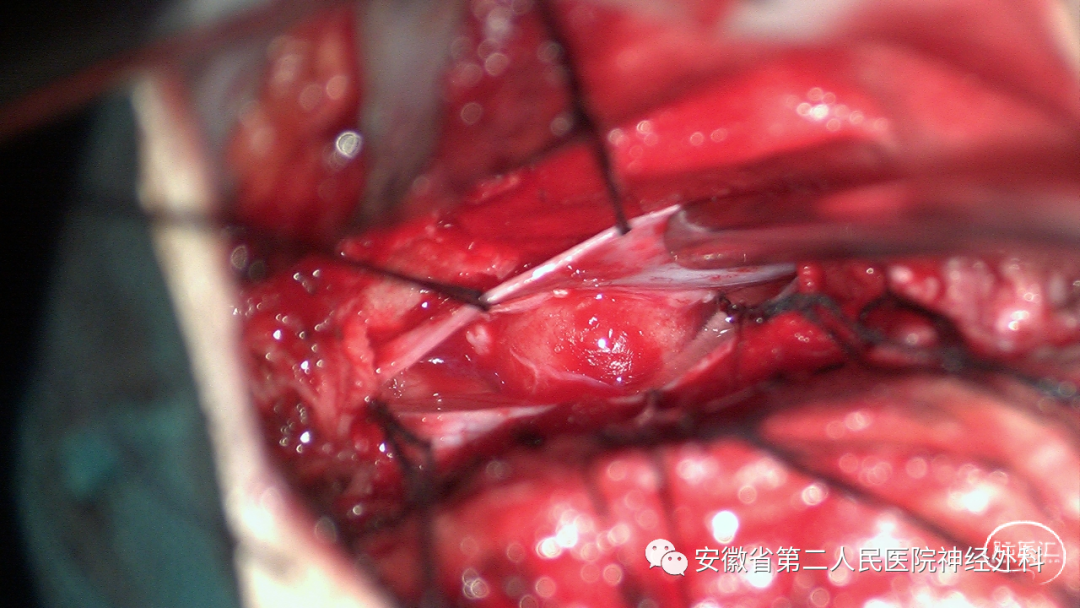

神经电生理监测下经右侧半椎板入路切除肿瘤

术中完整切除肿瘤